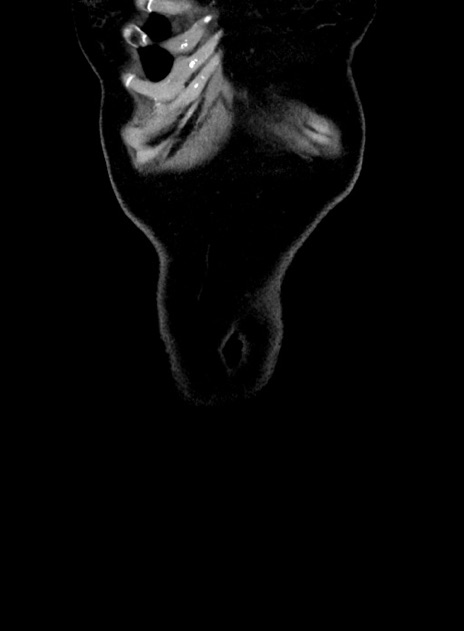

横断像

【症例】 60歳代女性

【主訴】むかつき、みぞおちの痛み

【現病歴】3日前よりむかつきがあり、食事がとれない。

【既往歴】糖尿病

【身体所見】発熱なし、心窩部圧痛軽度あるも、腹膜刺激症状なし。

【データ】WBC 7400、CRP 1.92